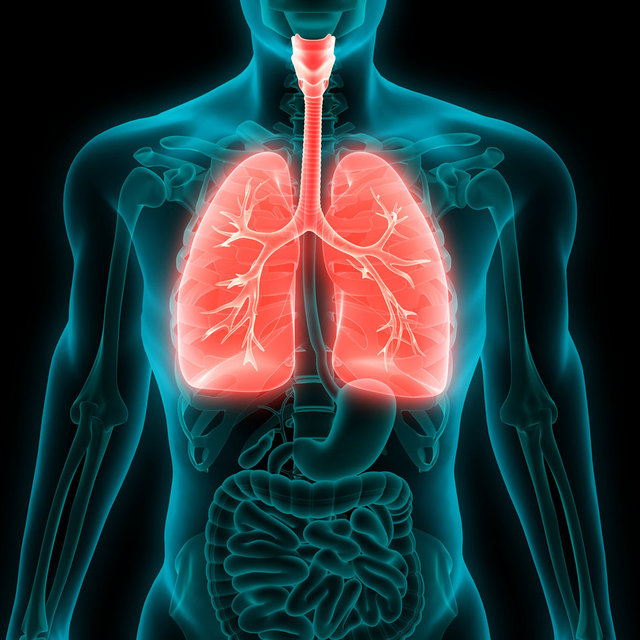

Haberler Sağlık Akciğer kanserinin 10 önemli sinyali! İnatçı öksürüğe dikkat! | Sağlık Haberleri

Akciğer kanserinin erken evresinde gelişen öksürük, başta solunum yolu enfeksiyonları olmak üzere pek çok hastalıkta görülebildiği için hastalar tarafından genellikle ihmal ediliyor. Ayrıca sigara kullanan hastalar da ‘Sigara öksürtüyor’ düşüncesiyle öksürük yakınmalarını önemsemiyor. Oysa özellikle iki haftadan uzun süren ve nedeni bilinmeyen inatçı öksürük akciğer kanserinin belirtisi olabiliyor. Teşhisin geç konulması ise tedavi şansının büyük oranda azalmasına neden oluyor.

Akciğer kanserinin belirtileri tümörün yerleşim yerine göre değişiklik gösterebiliyor. Bu yüzden genellikle başka nedenlerle çekilen tomografi veya akciğer filminde tesadüfen saptanıyor. Prof. Dr. Özlem Er, iki haftadan uzun süren ‘inatçı öksürük' başta olmak üzere aşağıda yer alan belirtilerde zaman kaybetmeden doktora başvurulması gerektiğine dikkat çekti.